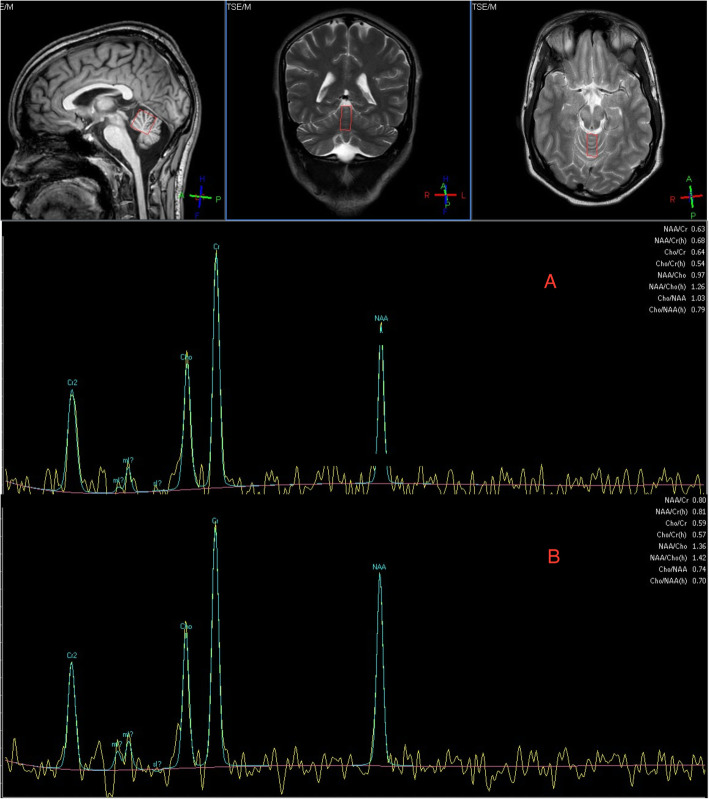

A 19-year-old man was referred to the Sheffield Ataxia Centre with a 12-month history of progressive slurred speech, difficulties swallowing, incoordination, imbalance and fluctuating abdominal pain and diarrhoea. Past medical history was remarkable for bacterial meningitis age 6 months. There was no significant family history. There was a history of ketamine, alprazolam and nitrous oxide misuse. At the time of referral he was using thickened fluids and required the assistance of one and a frame to mobilise. Physical examination demonstrated a cerebellar syndrome with pyramidal signs and pseudobulbar affect. There was broken pursuit and slight restriction of right lateral gaze, without nystagmus. Speech was dysarthric with slowed palatal and tongue movements. He was only able to say yes or no. There was generalised limb dysmetria. There was asymmetrical increased tone in the left upper and lower limbs with generalised brisk reflexes and plantar-flexor responses. Sensory testing for all modalities was normal. Gait was spastic and ataxic. A metabolic screen (including Wilson’s disease) and micronutrients were normal. Autoimmune (including anti-AQP4 and anti-MOG) and paraneoplastic antibodies were negative. IgA anti-transglutaminase type 6 (TG6) antibodies were strongly positive (11.1 U/ml, normal range < 4), suggestive of gluten sensitivity prone to neurological dysfunction. An initial lumbar puncture demonstrated an acellular CSF and CSF-restricted oligoclonal bands. An MRI head and MRS demonstrated mild cerebellar vermian and hemispheric atrophy with spectroscopic abnormalities (NAA/Cr superior vermis 0.63 and right cerebellar hemisphere 0.67) (Fig. 1 A). There were significant brainstem changes with signal change affecting the midbrain and extending into the thalamus and corticospinal tracts bilaterally, with no enhancement. 18FDG-PET demonstrated a region of increased uptake in the small bowel. Small bowel enteroscopy was macroscopically and microscopically normal, with no evidence of giardia, T Whipplei, acid fast bacillus or malignancy. Serum Cholestanol was normal. Muscle biopsy mitochondrial respiratory chain function, mitochondrial genetic analysis (MERRF, MELAS or NARP/MILS) and genetic testing for expansion mutations (Friedreich ataxia, Dentatorubral pallidoluysian atrophy and Spinocerebellar ataxia 1, 2, 3, 6, 7, 12 and 17) were unremarkable. EMG demonstrated an abnormal blink response (failure of second R2 response when undertaking blink reflex studies) suggesting a degree of cortical hyperexcitability. There were no other features of a peripheral neuropathy or continuous limb/paraspinal motor unit activity to suggest stiff person syndrome. Prior to referral, there was no observed response to an initial tapering course of steroids and azathioprine, which was stopped. He was diagnosed with GA and started a gluten free diet and mycophenolate (uptitrated to 1 g twice daily) following an induction course of IVIG, approximately 14 months after symptom onset. He was discharged to a neurorehabilitation unit. There was evidence of spectroscopic improvement on an MRI spectroscopy performed 3 months after treatment (NAA/Cr vermis 0.79 and right cerebellar 0.85) with persistent cerebellar atrophy and diencephalic signal changes (Fig. 1 B). Over 3 years of follow up there has been a dramatic and sustained improvement in speech and mobility. He is now able to have a normal conversation with minimal dysarthria and has started running again. There is evidence of a very subtle residual gait ataxia on independent tandem walking only.

Fig. 1.

Magnetic resonance spectroscopy (MRS) of case 2 pre-treatment (A) and after 1 year of immunotherapy and gluten free diet (B). Pre-treatment there is disproportionate vermian spectroscopic abnormalities of the N-acetyl aspartate/Creatine ratio (NAA/Cr) from the vermis (0.63, normal > 1) in the presence of only mild atrophy. MR spectroscopy is a sensitive marker of cerebellar dysfunction prior to the development of atrophy and correlates with clinical severity. Following treatment, there has been significant improvement in vermian spectroscopic abnormalities with NAA/Cr ratio 0.80 in parallel with clinical improvement. MR spectroscopy is a sensitive marker for monitoring disease progression and treatment response which is not possible with just volumetric imaging. The patient has made almost a full recovery with just very minor tandem walking difficulties